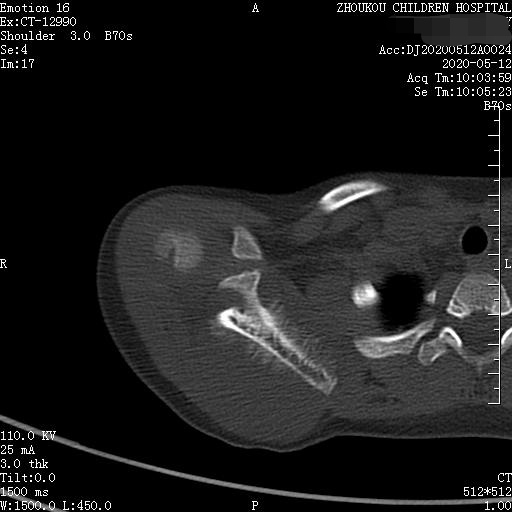

3岁女童以突发右侧肩胛部肿物来院检查,病人无发热、感冒症状,拍右肩关节正位片示:右侧肩关节肩胛岗上缘骨质密度欠均匀,建议CT进一步检查。

通过CT平扫发现:右侧肩胛骨骨质密度不均,骨质内可见“虫食样”低密度影,骨质边缘可见多发放射状骨针,呈“日光射线征”。周围软组织明显肿胀,肌间隙模糊。CT检查意见:考虑:右肩胛骨占位,骨肉瘤可能,不除外其它恶性肿瘤病变,请结合临床及相关检查注意复查。 影像鉴别诊断:骨肉瘤是指起源于骨间叶组织,遗留形成骨细胞直接形成骨样组织为特征的恶性肿瘤,是比较常见的骨恶性肿瘤,好发于十到二十岁青少年,骨肉瘤常见于管状骨,股骨远端胫骨近端最多见,表现为疼痛局部肿胀运动障碍,实验室检查都有碱性磷酸酶升高。